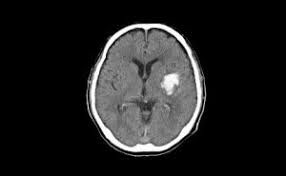

뇌출혈은 뇌 속의 혈관이 터지면서 혈액이 뇌조직 안에 고이는 상태를 말합니다. 주로 고혈압, 뇌동맥류 파열, 외상, 혈액응고장애 등이 원인이 됩니다. 뇌 내에 피가 고이면 뇌조직이 압박되거나 손상되어 심각한 장애를 일으킬 수 있습니다.

- 뇌내출혈(Intracerebral Hemorrhage): 뇌 실질 내에서 출혈 발생

MRI, CT 등 영상검사를 통해 조기에 발견할 수 있으며, 발견 시 수술 또는 코일 색전술 등 예방적 조치를 할 수 있습니다.